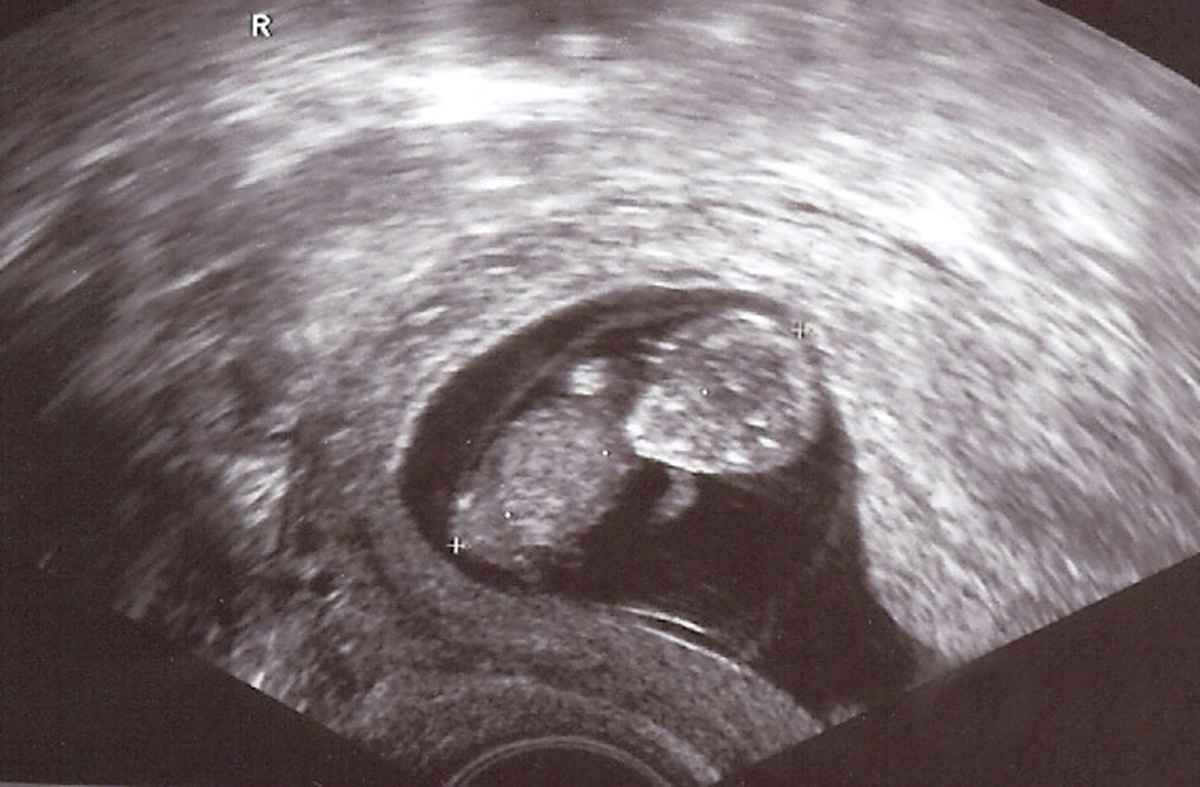

Ein Leben wächst heran

Ein kleines Wunder wenn man diese Aufnahme sieht, dass daraus ein Mensch wird. Mit allem Respeckt vor dieser Entwicklung. In der 10. Woche und 2,5 cm groß.